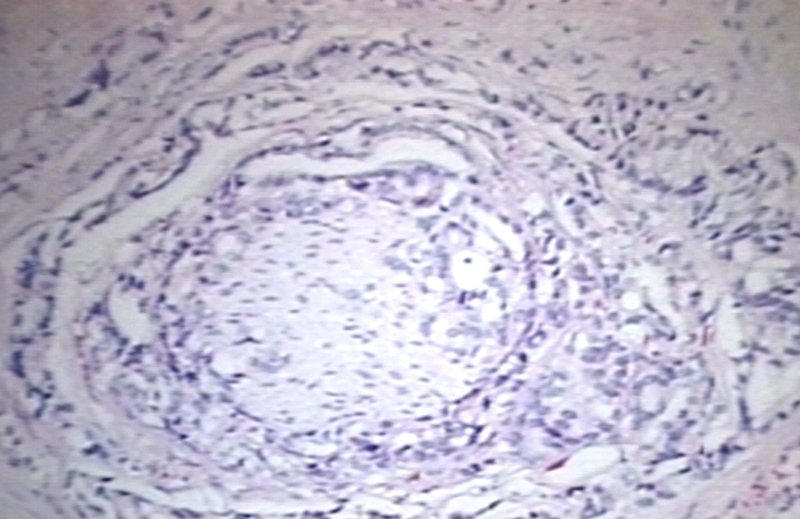

HISTOLOGY: PROSTATE: ADENOCARCINOMA, PERINEURAL INVASION